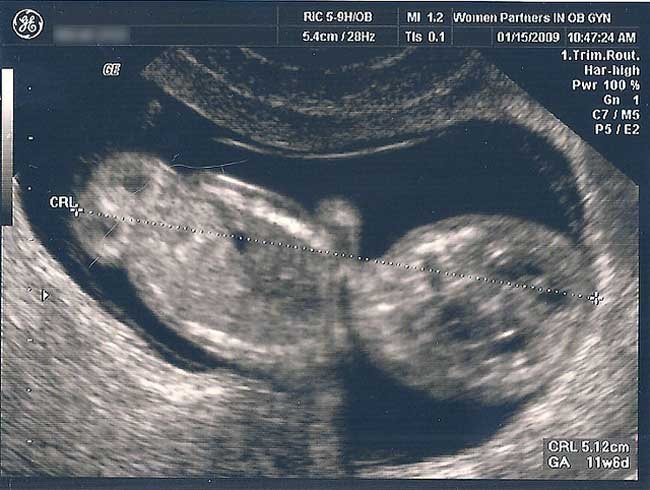

Para algunas, la primera ecografía será la de la confirmación del embarazo en las primeras semanas de gestación. Se mide el tamaño del feto, se observa la cantidad de embriones y el sitio de implantación del embrión para descartar un posible embarazo ectópico.

Sino, la primera seguramente se realizará en la semana 12 de gestación. Permite determinar si hay uno, dos o más embriones, conocer la posición en el útero, escuchar los latidos cardíacos y medir al feto para determinar si se ajusta al tiempo real de gestación.

También se realiza la medición del pliegue nucal, el marcador ecográfico precoz más sensible y específico de sospecha de Trismomía 21 o Síndrome de Down.